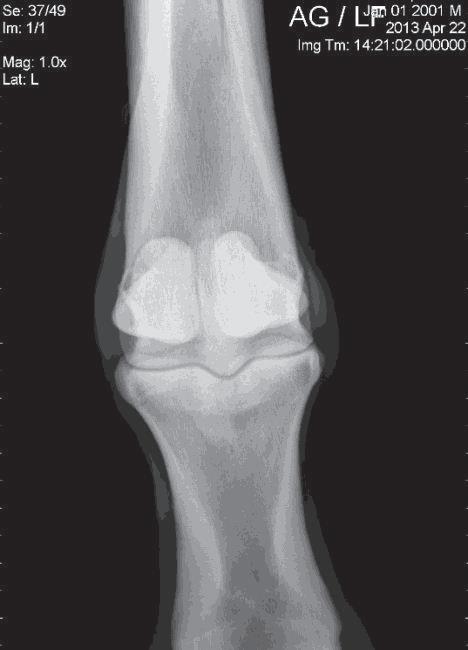

Knowledge of the discipline in which the horse is to function is essential in order to make appropriate decisions related to imaging. With the English sport horse or Western performance horse, certain common lameness issues are known to occur more frequently, and the choice of what regions to radiograph should be based on likely probability. Additionally, any other skeletal fi ndings that raise concern during the resting physical and exercise examinations should also be evaluated. Good positioning and technique are critical for consistent evaluations.1 Radiographic examination may expose old problems that have since resolved. Some injuries, such as suspensory enthesopathies, will remain radiographically evident but may predispose to injury in the future. Having access to previous radiographs can be extremely valuable in the assessment of the significance of abnormal fi ndings. For example, a proximal plantar P1 fragment in a hind fetlock may not represent as much risk for future hind limb lameness when found in a 10-year-old jumper if it was known to be there when the horse was four years old (Figure 1.). Comparison to previous radiographs may also help predict the long term significance and progression of some lesions as well. For example, moderate osteoarthritic changes associated with a pastern joint in a warmblood found in today’s examination may carry less significance if known to have been there on radiographs two years prior.

Figure 12: Purchase examination image on the left and lameness examination image on the right six months post-purchase that blocked to an abaxial sesamoid block. Area of sclerosis and region of subchondral injury of the sagittal groove of the proximal first phalanx (P1) which may be enhanced by a slightly flatter beam angle.

Image courtesy of Dr. Richard D. Mitchell.